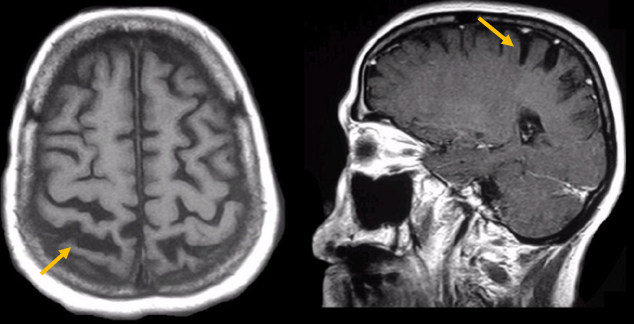

진행 핵상 마비는 대표적인 파킨슨 증후군 중의 하나입니다. 파킨슨병과 다른 점은 질병의 초기부터 중심을 잡기 어려운 체위 불안정이 나타나 자주 넘어진다는 것입니다. 파킨슨병의 경우 질병이 상당히 진행된 뒤에 체위 불안정이 나타납니다. 또한 진행 핵상 마비에서는 목 주위 근육을 비롯한 몸 중심 근육의 경축이 나타나, 목을 뒤로 젖히면서 걷는 모습이 보입니다. 그리고 눈의 운동을 조절하는 기능에 장애가 나타나 아래쪽을 바라보는 데 문제가 생겨 계단을 내려갈 때 어려움을 겪는 경우가 많습니다. 진행 핵상 마비가 의심되는 경우, 뇌 자기공명영상(MRI)에서 중뇌의 위축이 비정상적으로 심하게 나타나는 소견을 확인하거나, 뇌포도당 양전자 단층촬영(PET)에서 전두엽과 중뇌의 대사 기능이 저하된 소견을 확인하여 진단에 참고할 수 있습니다.

[진행핵상마비 환자의 뇌자기공명영상에서 확인되는 중뇌 위축 소견]